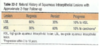

Quais as 3 classificações da fase de displasia do colo uterino?

Neoplasia intraepitelial cervical ou escamosa

SIL ou NIC 1

SIL ou NIC 2

SIL ou NIC 3 ou carcinoma in situ

Como ocorre a progressão do câncer de colo uterino NIC 1, 2 e 3?

NIC1 não tende a evoluir** (estagnam e são destruídas pelo sistema imune) = **LSIL (de baixo grau)

NIC 2 e 3 costumam já surgirem em seu respectivo estágio e possuem uma grnade chance de evoluírem para a fase invasora = HSIL (de alto grau)